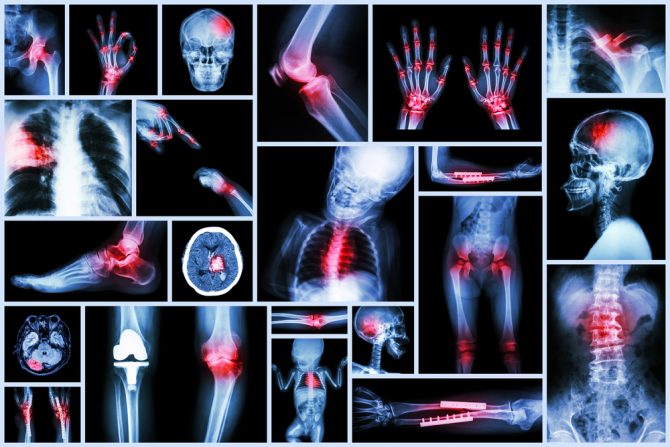

Mnoga stanja mogu da izazovu bol svih zglobova odjednom i najčešći uzroci tog stanja su infekcija, zapaljenske bolesti i komplikacija nekog zdravstvenog stanja. Nelagodnost i bol u zglobovima obično se oseća u rukama, stopalima, kukovima, kolenima ili kičmi. Bol može da bude stalna ili da "dođe pa prođe". Takođe, bol svih zglobova može da bude  indikacija komplikacija nakon neke bolesti, kao što je post-virusni sindrom ili reaktivni artritis.

Lekari izdvajaju 10 mogućih uzroka zbog kojih se osećamo "slomljeno", zbog kojih nas boli svaki zglob i mišić, i skoro svaki deo tela.